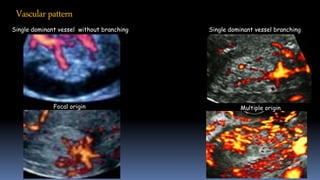

Vascularpattern

Single dominant vessel without branching Single dominant vessel branching

Focal origin Multiple origin

Vascularpattern Single dominant vesselwithout branching Single dominant vessel branching Focal origin Multiple origin